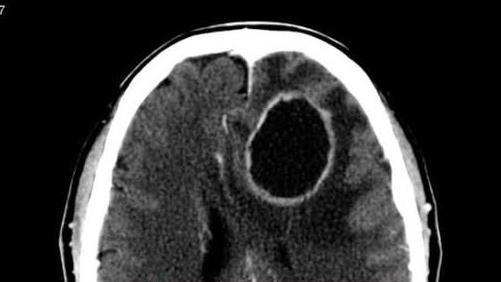

2. 危險三角區

- 鼻子、嘴唇和下巴之間的區域被稱為「危險三角區」,因為這裡的血管與大腦相通,若鼻子感染嚴重,細菌可能會由血管感染大腦,導致嚴重後果,甚至危及生命。縱使機率不高,但亦曾出現過案例,所以有一定風險。